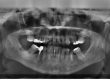

Dental Crowding

When your teeth are crowded in your mouth, this is more than an appearance issue. Dental crowding can cause jaw disorders or bite issues (overbite or underbite).

Several options can be used to treat dental crowding. Your dentist may suggest you visit an orthodontist to discuss the use of braces or Invisalign to fix your teeth.